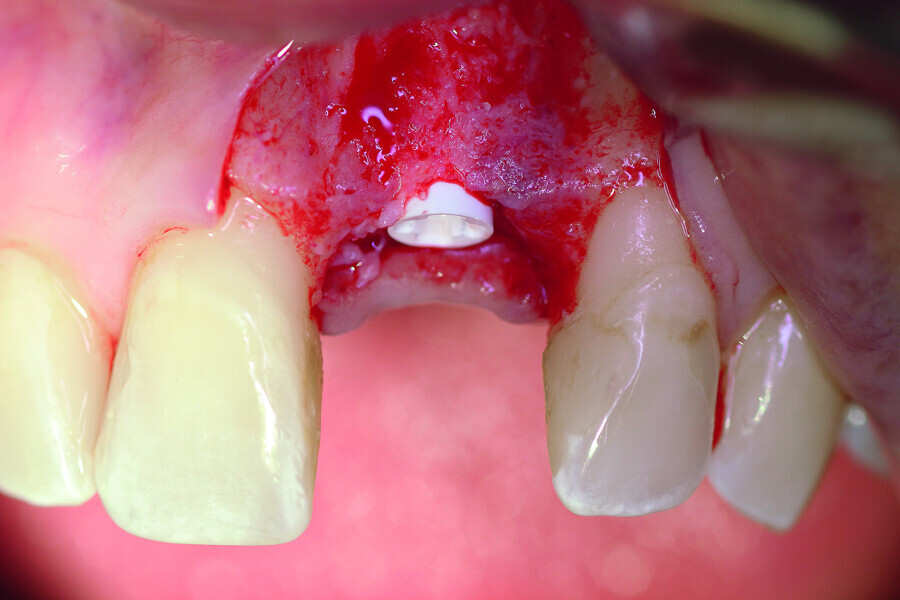

Fig. 5a: A two-piece ceramic implant was inserted.

Fig. 5b: A two-piece ceramic implant was inserted.